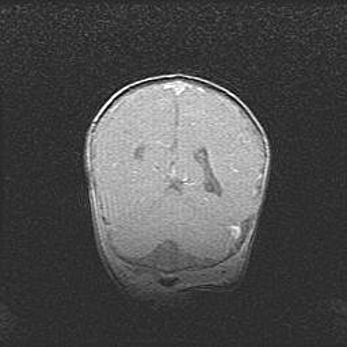

Лейкомаляция с кистозно-глиозной дегенерацией головного мозга.

Возраст: 2 месяца 25 дней

Вес: 6400 г

Окружность головы: 40 см

Срок гестации: 41 неделя

Лейкомаляцию относят к ишемически-гипоксическим повреждениям головного мозга, диагностируемым у новорожденных. При лейкомаляции в головном мозге обнаруживают очаги некроза, возникшие после тяжелой гипоксии и нарушения кровотока. В процессе морфогенеза очаги проходят три стадии: 1) развития некроза, 2) резорбции и 3) формирования глиозного рубца или кисты. Перивентрикулярная лейкомаляция (ПЛ) встречается примерно в 12% случаев среди новорожденных, обычно – у недоношенных детей, причем, частота ее зависит от массы, с которой младенец появился на свет. Наибольшее число малышей страдает лейкомаляцией, если масса при рождении 1500-2500 г.